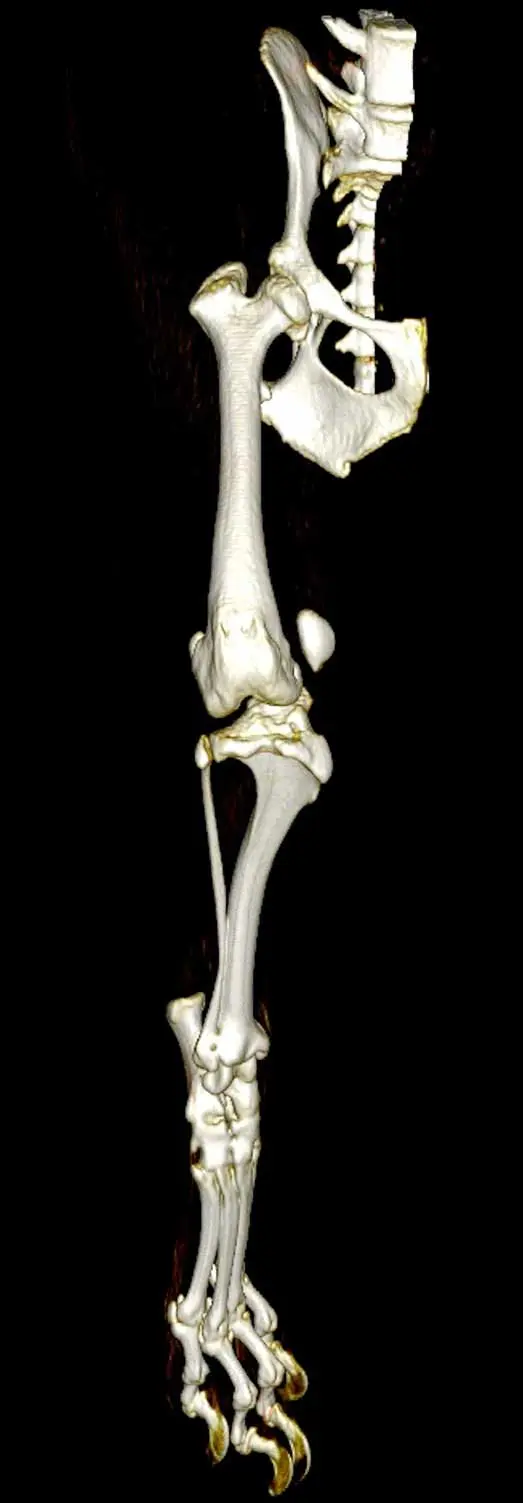

In the earlier literature regarding high-grade PL, a rotational deformity in the stifle joint, with the tibia internally rotated with respect to the femur, is often described (Figure 4).

Compensatory external torsion is often present in the tibia. Derotation of the stifle is under-reported in the literature (Chen et al, 2021; Petazzoni et al, 2026). The author’s caseload includes a large number of cases with this particular deformity, which is frequently addressed through stifle derotation as a standalone intervention or in combination with trochlear groove deepening. Further data regarding stifle rotational deformity and what may be achieved through derotation is required, and will hopefully become more available in the near future.

The role of advanced imaging

One of the most significant recent developments in understanding PL is the application of CT imaging. Three-dimensional imaging (CT) and computer modelling allows us to assess bone anatomy and stifle joint alignment with greater accuracy than 2D imaging.

However, as we learn more about the anatomy and how to assess it, we start to need protocols for measurement of the aspects we feel are important, as well as reference ranges for these measurements to determine what is normal and what is not.

Agreed protocols for what to measure and how among the profession do not exist, and complexity increases when, for example, awake CT (Tomo et al, 2022) is added into the fray, apparently giving greater insight than static CT can.

CT imaging enables accurate measurement of:

- femoral neck inclination

- femoral torsional deformity

- stifle rotational deformity

- trochlear orientation and depth

- tibial tuberosity location and shape

- tibial torsional deformity

While CT is not necessary for every case, it is increasingly difficult to justify complex reconstructive surgery without detailed understanding of limb geometry. As access to advanced imaging improves, expectations of surgical planning will continue to evolve.